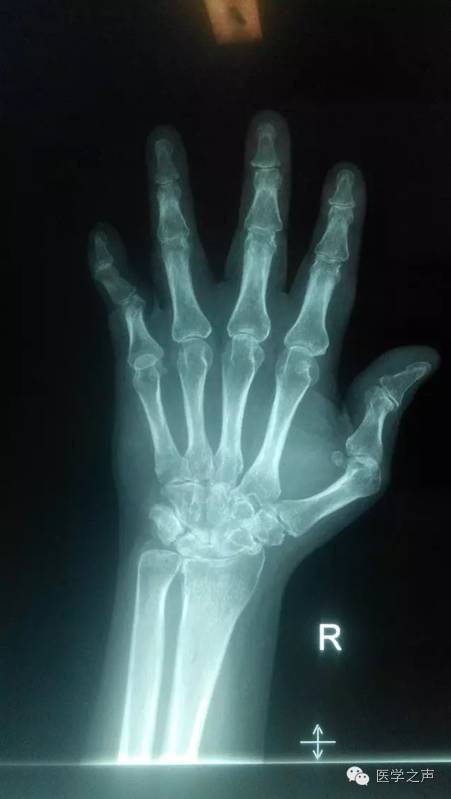

骨软骨瘤-恶变